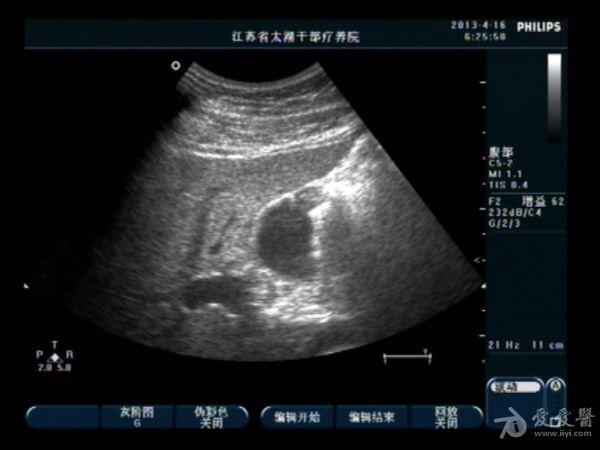

胆囊底部稍低回声区,胆泥沉积?胆囊癌不像吧?,请分析

男性,40,无右上腹痛

变换**,轻轻地敲打胆囊区,如果是胆泥块,会被敲的松散